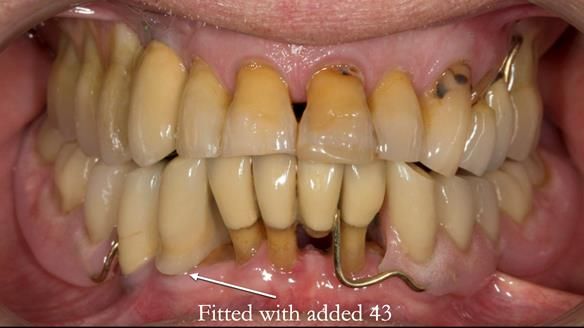

In 2022, tooth 43 fractured.

An artificial tooth was added to the RPD

by welding a cobalt–chrome tag to the bar

and adding the tooth.

The denture continued to function extremely well.

This case was always about function, not aesthetics.

Ken’s teeth were never going to look perfect.

There were stained composites, old restorations, and obvious wear.

That was accepted from the outset.

The way Rowan lengthened the teeth — particularly in the upper RPD — to match the existing gingival recession on the remaining teeth was superb. The dentures sit naturally within the context of the rest of the mouth.